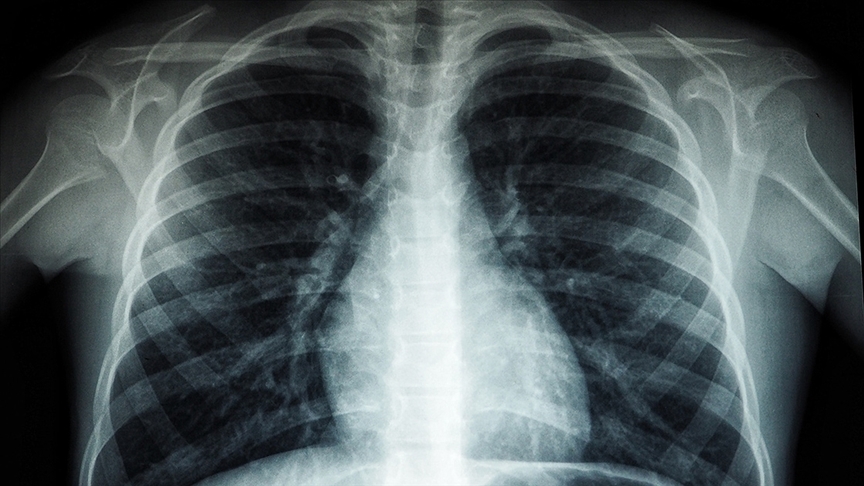

82 yaşındaki akciğer hastası solunum cihazı olmadan adım atamıyordu. Kars'ta uygulanan bu tedavi ile artık egzersizlere başladı.

Kars'ta Kafkas Üniversitesi Sağlık Araştırma ve Uygulama Merkezi'nde gördüğü tedaviyle 5 yıldır kullandığı oksijen cihazından kurtulan 82 yaşındaki akciğer hastası, egzersiz ve yürüyüşle dinç kalmaya çalışıyor.

Sarıkamış ilçesinde yaşayan 2 çocuk babası Ahmet Çağır, 2019'da akciğerlerinde enfeksiyon gelişmesi nedeniyle bir süre tedavi gördü. Bir yere giderken ihtiyaçlarını ailesinin yardımıyla ve sürekli solunum cihazına bağlı halde sürdüren Çağır, bir süre önce Kafkas Üniversitesi Sağlık Araştırma ve Uygulama Merkezi'nde görevli göğüs hastalıkları uzmanı Dr. Çağrı Atasoy'a başvurdu.

Merkezde oluşturulan "İnterstisyel Akciğer Hastalıkları Konseyi"nce Çağır'ın hastalığının karbonmonoksit difüzyon testi cihazı yardımıyla yapılan tetkiklerde "akciğer sertleşmesi" olduğu belirlendi. İki gün yatarak tedavi gördükten sonra antifibrotik ilaç başlanılan ve 3 ay takip edilen Çağır, olumlu geçen tedavisinin ardından rahat nefes almanın ve oksijen cihazı olmadan hayatını sürdürmenin mutluluğunu yaşıyor. Çağır, ilerleyen yaşına rağmen ilçede yürüyüşe çıkmadan önce egzersiz de yaparak dinç kalmaya çalışıyor.

Çağır, ilerleyen yaşına rağmen ilçede yürüyüşe çıkmadan önce egzersiz de yaparak dinç kalmaya çalışıyor. Dr. Çağrı Atasoy, AA muhabirine, interstisyel akciğer hastalıklarının akciğerde sertleşmeyle giden, nadir gözüken ve yakın zamana kadar tedavisi olmayan hastalık grubu olduğunu söyledi. Yeni geliştirilen ilaçlarla artık bu hastalıkta ilerlemeyi durdurabildiklerini ifade eden Atasoy, gelişen teknolojiyle hastalıkların tedavisinde cihazların yardımcı olduğunu, interstisyel akciğer hastalıkları için de hastaneye karbonmonoksit difüzyon cihazı alındığını anlattı.

Merkezin solunum testi laboratuvarı, son teknolojik cihazlarla donatıldı Atasoy, hava kirliliği, sigara içme, ileri yaş gibi etkenlerin akciğer hastalığını tetiklediğini, tedavi açısından hastalığın teşhisinin net olarak bilinmesi gerektiğini belirterek, şunları kaydetti: "Cihazı hastalığın tanısı ve tedavi takibinde kullanıyoruz. Solunum testi laboratuvarımızda, solunum fonksiyon testi, akciğerlerdeki gaz alışverişini değerlendirmek için yapılan DLCO ve çeşitli akciğer hastalıklarının tanı ve tedavisinde solunum yollarını detaylı gören bronkosopi cihazları ve aynı zamanda son teknolojik Endobronşiyal Ultrasonografi (EBUS) gibi cihazlara sahibiz. Kanda romatolojik tetkiklere bakıyoruz, romatoloji, göğüs cerrahi ve göğüs hastalıkları olarak bu kompleks hastalık durumuna tanı koyup, tedavi vermeye çalışıyoruz."